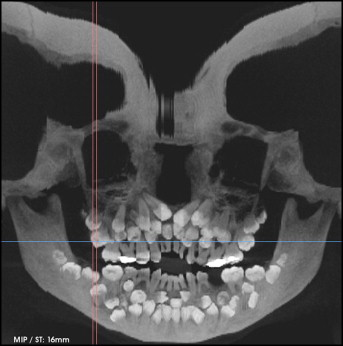

Qua khám trong miệng, các bác sĩ ghi nhận chỉ có 5 răng vĩnh viễn đã mọc. Trong khi đó, các răng sữa vẫn còn tồn tại khá nhiều. Nhằm đánh giá toàn diện hơn tình trạng răng miệng của bệnh nhi, các bác sĩ đã chỉ định chụp phim toàn cảnh và phim sọ nghiêng. Kết quả phim cho thấy một bất thường nghiêm trọng: sự hiện diện của rất nhiều răng thừa.

Hình chụp X-quang của bệnh nhi

Cụ thể, kết quả chụp đã cho thấy bệnh nhân có tổng cộng 81 chiếc răng, bao gồm: 18 răng sữa, 32 răng vĩnh viễn và 31 răng thừa. Các hình ảnh cũng cho thấy nhiều răng có hình thể bất thường khiến việc phân biệt giữa răng thường và răng thừa trở nên vô cùng khó khăn.